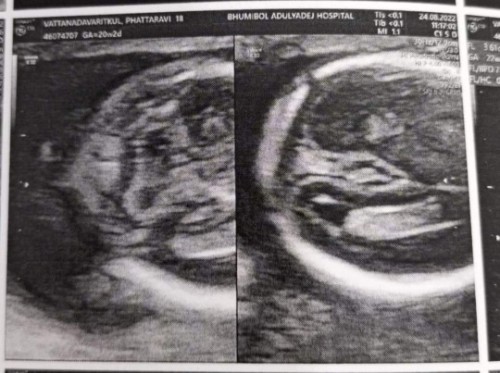

ไปซาวน์มาวันนี้หมอบอกเป็นผู้หญิง แบบนี้มีโอกาสที่จะเป็นผู้ชายมั้ยคะ

ภาพไม่ชัดคะกี่วีคแล้ว